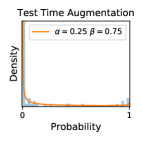

5.1 Distribution of Uncertainty Scores

Distribution of Uncertainty Scores Across Different Severity Levels As explained in Section 3, each uncertainty metric essentially defines an order/ranking among the data points. We conducted an analysis to better understand what data will be assigned high uncertainty under a particular uncertainty metric . Picking out the highest ranked data points (), we calculated the ratio of data points from each SL. Figure 4 summarizes the results as box plots for the Kaggle-DR and the Messidor-2 datasets; additional detailed statistics can be found in Table S.1 in the supplementary materials. From the plot and table, SL1 & SL2 examples account for a higher proportion among the top-ranked uncertain examples across the three ensemble methods. This finding matches our intuition that incipient disease examples (SL1 & SL2) are more likely to be considered uncertain by ensemble methods due to their ambiguity.

Comparing the three ensemble methods in Figure 4, the stacking ensemble method has the highest ratios of SL1 & SL2 data among the high-uncertainty examples it identified under both mean and var. TTA showed slightly better performance than MC-dropout but still falls behind the stacking ensemble method. Considering the fact that SL0 examples accounted for the majority of the dataset, the stacking ensemble method was much more precise (specific) in selecting truly ambiguous data points that were difficult to classify. From Figure 3, we can also see that the stacking ensemble method greatly outperformed the other two methods in finding false negatives under both mean and var uncertainty metrics.

As discussed in Section 5.1 and Section 5.3 in the main paper, the mean metric and the stacking ensemble will have better performance in the precision (specificity) on the ambiguous data. Here, more detailed results are shown in Figures S.3 & S.6 and Table S.1. Figures S.3 & S.4 show the histograms of the uncertainty score for Kaggle-DR and Messidor-2 datasets that are the in-distribution (i.d.) dataset in our experiment and FigureS.5 & S.6 show the histograms for ImageNet and CIFAR-10 datasets, which is the o.o.d. datasets in our experiment. Each group of histograms contains results from the three evaluated ensemble methods (stacking ensemble, MC-dropout and TTA) and the three uncertainty metrics (mean, var and kl). Additional detailed results not displayed in Figure 4 can be found in Table S.1, which shows the proportion of the data of different SLs varies across different . For comparison, we also included in Table S.1 the results from single learners, and the proportions of data of different SLs (before any selection was made).